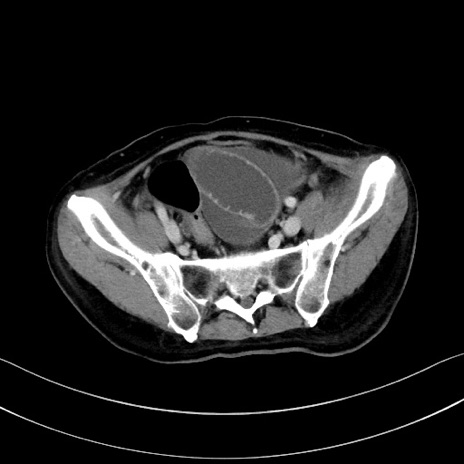

症例28(横断像)

【症例】60歳代男性

【現病歴】胃癌にて胃全摘後。食思不振が悪化し、夜中に嘔吐することがある。

【既往歴】胃癌、胃全摘、脾摘、胆摘後